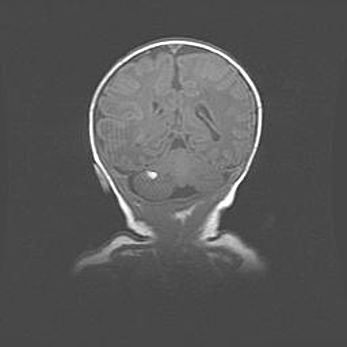

Мальформация Денди-Уокера. Киста задней черепной ямки.

Агенезия мозолистого тела.

Возраст: 2,5 месяца

Вес: 2420 г

Пол: женский

Окружность головы: 37 см

Срок гестации: 32 недели

Мальформация Денди—Уокера — редкий вид патологии ЦНС, представляющий собой врожденный порок развития каудального отдела ствола и червя мозжечка, ведущий к неполному раскрытию срединной (Мажанди) и латеральных (Лушка) апертур IV желудочка мозга. Для этогно синдрома характерна триада симптомов: гипотрофия червя мозжечка и/или полушарий мозжечка, кисты задней черепной ямки, гидроцефалия различной степени. В 70% случаев порок сочетается и с другими аномалиями головного мозга, в частности с агенезией мозолистого тела.